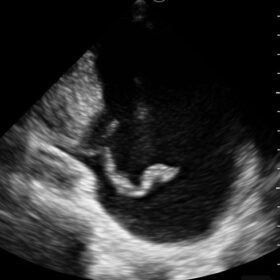

Mindray I3P WiFi Probe Image Gallery and Videos

Display mode: B, B/M, and Color, PW, PDI